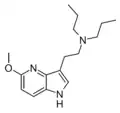

4-Aza-5-MeO-DPT (P-11) | N-[2-(5-methoxy-1H-pyrrolo[3,2-b]pyridin-3-yl)ethyl]-N-propylpropan-1-amine | |

|

5-Aza-4-MeO-DiPT (P-36) | N-[2-(4-methoxy-1H-pyrrolo[3,2-c]pyridin-3-yl)ethyl]-N-(propan-2-yl)propan-2-amine | |

|